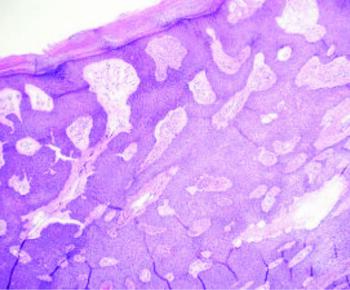

The initial working diagnosis was verruca, but we chose to perform a biopsy to rule out atypical malignancy. We administered local anesthesia to the dorsal aspect of the foot with three milliliters of 1% lidocaine plain before performing a shave biopsy of the lesion with a #15 blade. Upon removal of the lesion, there was significant bleeding, and the base appeared more erythematous, but there was still no indication of infection. The lesion was placed in formalin and sent for histological examination, which reported a “monomorphous proliferation of cuboidal, basophilic cells emanating from the undersurface of the epithelium.” It also demonstrated “small, duct-like laminae … within sheets of neoplastic cells.” The examination did not identify histologic features of melanoma.

As dermoscopy can be unreliable and many physicians lack the necessary tools and skills to utilize it, a biopsy of the lesion is frequently helpful in obtaining a definitive diagnosis. Utilizing a shave, punch, or other incisional biopsy technique, one can send the lesion specimen in formalin for histological examination, which will show a well-circumscribed tumor composed of cuboidal keratinocytes (ie poroidal cells) that extend from the basal layer into the dermis.1 The cells have a non-palisading pattern despite being involved in the sweat gland duct, and the nuclei will be monomorphous and ovoid with discrete nucleoli. The cytoplasm is usually eosinophilic, and the cells usually stain positively with periodic acid-Schiff. Carcinoembryonic antigen (CEA) immunostaining can assist in confirmation of the ductal differentiation.3